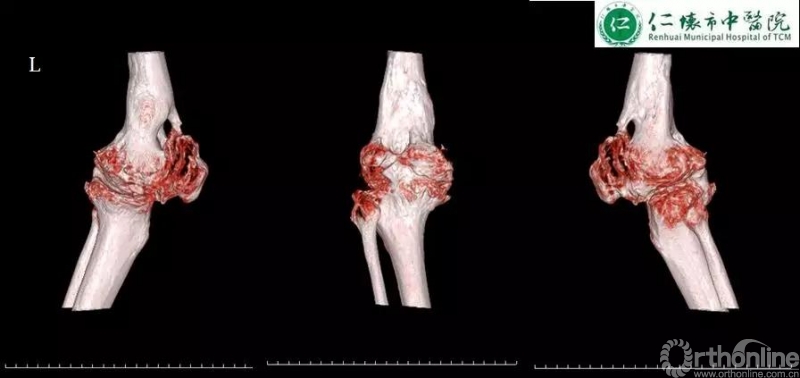

课程分享结束后,进入病例分享环节,四家与会医院分别展示各自病例并就术中存疑和李子剑教授探讨取经。仁怀市中医院分享了一例经典的使用ACCK假体复杂右膝关节置换手术:

术前影像:

李子剑教授对仁怀市中医院这例手术的术前规划方案和假体选择表示充分的肯定,对术后力线及假体位置同样表示赞赏。对于仁怀市中医院各位主任提出的关于未来左膝关节置换的相关问题,李教授给出了使用定制化导板截骨的中肯建议,并分别分析了ACCK,AHK和肿瘤假体在这例病例中应用的可能性及利弊,各位专家集思广益,不断碰撞出学术的火花。